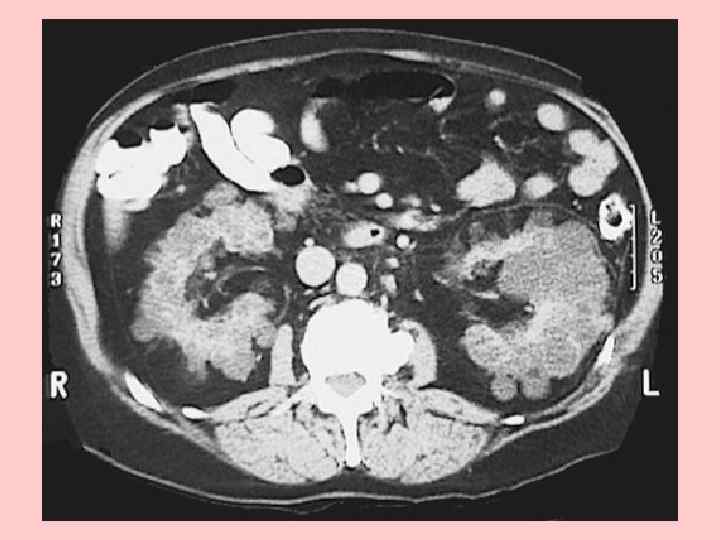

В основе инструментальной диагностики этого заболевания лежит выявление кист — основного клинического маркера поликистоза почек. С этой целью в настоящее время широко используют современные методы диагностики почечных кист — ультразвуковое исследование, сцинтиграфию и компьютерную томографию. При ультразвуковом исследовании и сцинтиграфии выявляются кисты размером более 1, 5 см, при компьютерной томографии — более мелкие (от 0, 5 мм).

Для лиц с отягощенной наследственностью критерием диагноза является один из приведенных ниже вариантов соотношения количества кист в почках и возраста, даже при отсутствии клинических признаков болезни [Ravine D. et al. , 1994]: • наличие 2 кист в одной или обеих почках в возрасте до 30 лет; • наличие по 2 кисты в каждой почке в возрасте 30— 59 лет; • наличие не менее 4 кист в каждой почке в возрасте старше 60 лет.

Кисты в почках и печени являются определяющим фактором для всей группы кистозных болезней. Кисты представляют собой наполненные жидкостью структуры различной величины, выстланные одним слоем измененного канальцевого эпителия. Кисты обнаруживают: в корковом и мозговом слое почек, в области лоханок почек и окололоханочной области, реже на полюсах почки. Размер кист и количество жидкости в них широко варьируют: малые кисты (менее 2 мм в диаметре) содержат, как правило, не более 3 мл жидкости, в то время как в больших кистах количество жидкости может исчисляться литрами.

По мере прогрессирования болезни число кист возрастает, увеличиваются их размер и соответственно размер почек, поверхность которых становится неровной, похожей на “виноградную кисть”. Почки при поликистозе могут достигать в длину 40 см и весить более 8 кг [Пытель Ю. А. , 1995].